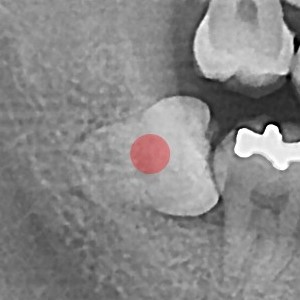

智齿拔除 部分埋伏智齿